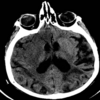

What imaging is used in this picture? [1]

dopamine transporter (DaT) - DaT scan